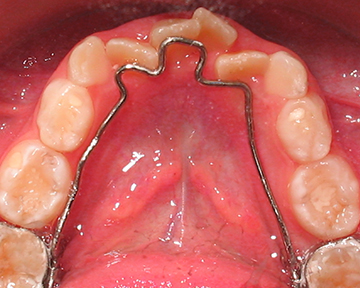

Esto se puede corregir a través de procedimientos capaces de eliminar o reducir su severidad impidiendo que la mala mordida se instale. El objetivo es orientar la salida de los dientes permanentes, para que salgan en los espacios que deben salir.

La idea es que a través de la instalación de aparatos sencillos y fijos (no removibles) el diente permanente realice su erupción de una forma adecuada.